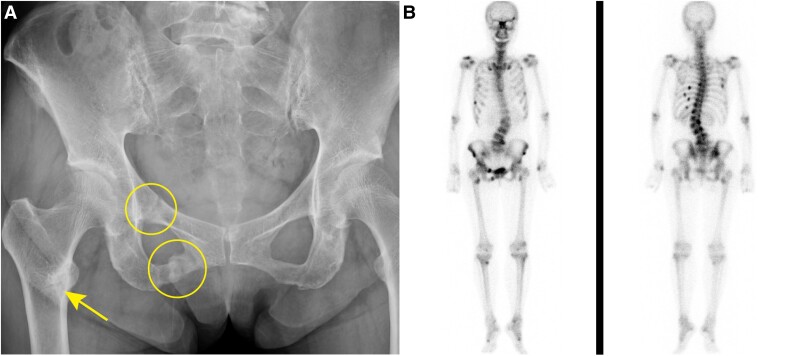

Tumor-induced osteomalacia is characterized by hypophosphatemia and fragility fractures caused by fibroblast growth factor 23 (FGF23)-producing tumors. We report a case of tumor-induced osteomalacia in which the tumor location could be determined by gallium 68 (68Ga)-DOTATOC positron emission tomography (PET)/computed tomography (CT). A 74-year-old woman had recurrent fractures and bone pain. Blood tests showed hypophosphatemia and elevated serum alkaline phosphatase and FGF23 levels and CT and bone scintigraphy showed multiple bone fractures. Tumor-induced osteomalacia was therefore suspected. Indium 111 (111In)-pentetreotide scintigraphy showed focus of increased activity in the head, and CT and magnetic resonance images showed a mass-like lesion in the posterior ethmoidal sinus. However, in systemic venous sampling, serum FGF23 level was highest in the left common iliac vein. 68Ga-DOTATOC PET/CT clearly demonstrated focal uptake in the left anterior inferior iliac spine consistent with systemic venous sampling. Retrospectively analyzed, focal uptake in the head was considered to be a physiological uptake in the pituitary gland. The tumor was resected and the pathological diagnosis was phosphaturic mesenchymal tumor. A combination of systemic venous sampling and 68Ga-DOTATOC PET/CT was useful in detection of a small FGF23-producing tumor. Precise tumor localization in such cases requires careful interpretation of scintigraphy.